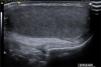

A boy aged 12 years was referred for assessment of testicular asymmetry identified during a routine check-up (left-side volume of 9mL compared to right-side volume of 5mL, measured with an orchidometer). The testicular ultrasound examination revealed a normal right testis (Fig. 1). In the left side, the scan revealed the presence of two ovoid masses with a homogeneous medium-level echotexture, with the mass located cranially measuring 1.3mL and the distal mass measuring 4.8mL (Fig. 2). Both exhibited a hyperechoic area at the center (mediastinum testis) with a thin hyperechoic margin (tunica albuginea) (Fig. 3). The patient received a diagnosis of polyorchidism or left supernumerary testis.

In most cases, the cardinal feature leading to its detection is an asymptomatic scrotal mass. Sonography is the imaging technique of choice, allowing visualization of the supernumerary testis, usually smaller than the contralateral testis, with normal sonographic appearance and preserved blood flow on Doppler.